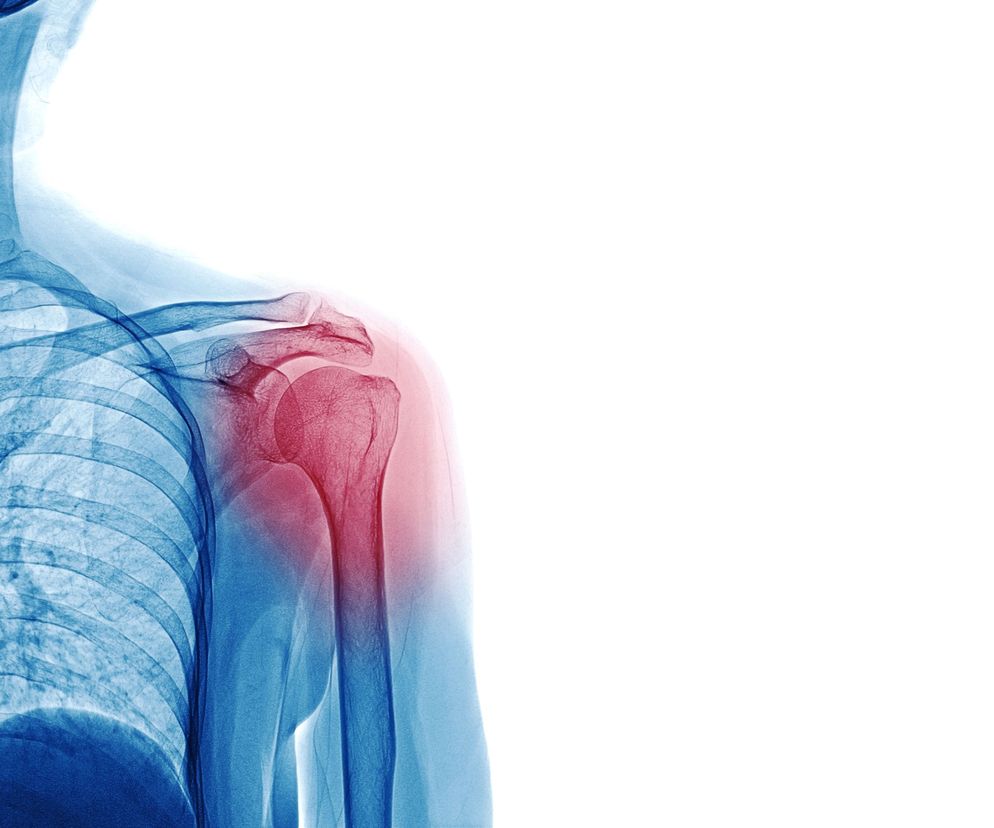

Staw ramienny to największy staw kończyny górnej, który łączy kość ramienną z obręczą barkową. Jako staw kulisty umożliwia bardzo szeroki zakres ruchu we wszystkich płaszczyznach. Uszkodzenia stawu ramiennego mogą z jednej strony generować ból i ograniczać ruchomość w stawie, a z drugiej strony wywoływać niestabilność związaną ze zbytnim rozluźnieniem i rozciągnięciem okalających go struktur.

Staw ramienny jest podatny na urazy i kontuzje, ponieważ jest dość intensywnie używany, a przez sportowców - często nadużywany. To w połączeniu z dużym zakresem ruchomości we wszystkich kierunkach oraz mnogością okalających go struktur sprawia, że łatwo go uszkodzić.